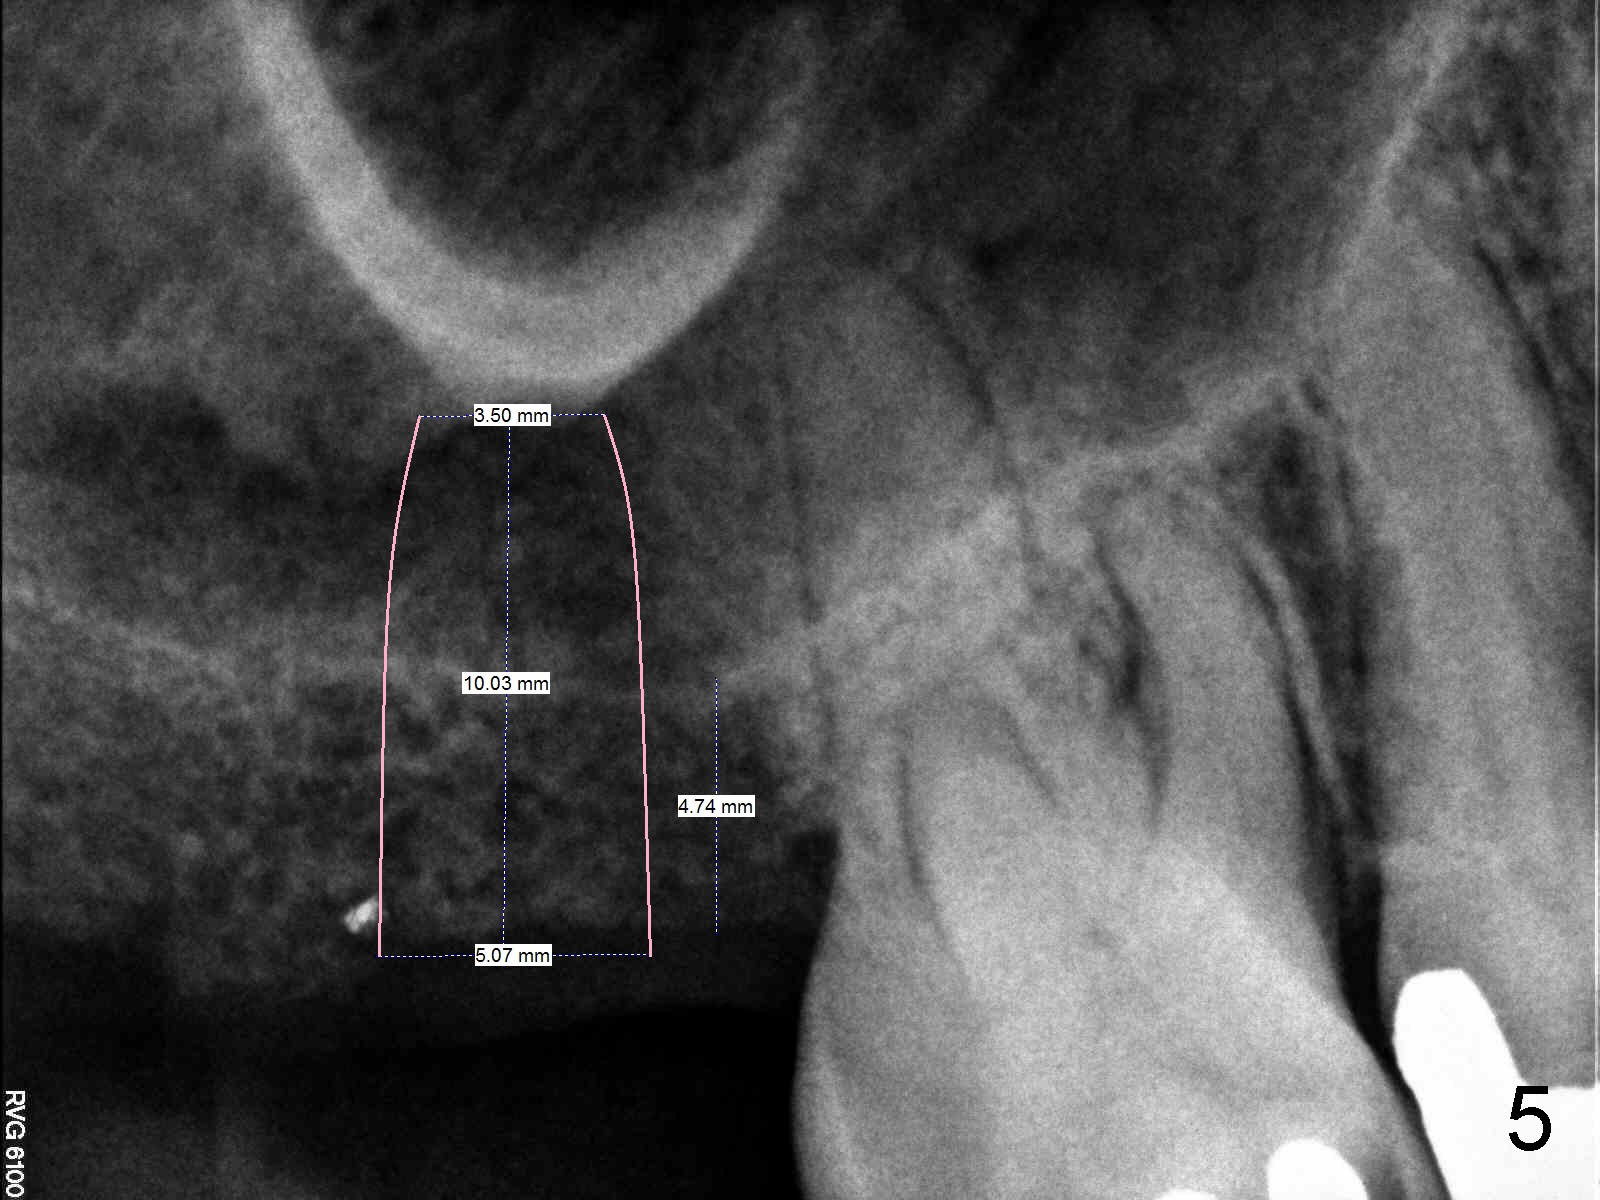

A 60-year-old man requests restoration of the missing upper right 2nd molar (Fig.1).  It appears that the bone height is limited (between white and red arrowheads, approximately 5 mm (Fig.5)).  Study of the sinus floor in association with the roots of the 1st molar reveals that the palatal root (P) appears inside the sinus.  In fact it is not.  Therefore there is bone apparently inside the sinus.

Anyway, a 1.6 mm pilot drill or 2 mm osteotome may be used to initiate osteotomy at the depth of 4-5 mm (Fig.3).  An explorer is used to check whether the sinus membrane has been reached or not.  As the diameter of bone expanders or osteotomes increases, the depth of the osteotomy increases (Fig.4), pushing the native bone into the sinus.  Each step check sinus membrane integrity by using an explorer or doing nose blowing test.  The implant can also push more bone upward when it is being placed (Fig.5).  Combined lateral and crestal sinus lift is not recommended in this case because of limited access.

CBCT confirms the bone height (4.4 mm) (Fig.6).  Bone density is 200-400 Hounsfield units.  The best new is sufficient bone width (7 mm) buccolingually.